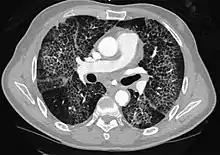

CT image showing ground-glass opacification in the posterior of the right lung (screen left). - Measles